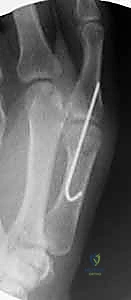

- الأشعة السينية (X-rays): ضرورية لاستبعاد وجود كسور مصاحبة (مثل الكسر القلعي Avulsion Fracture حيث ينفصل جزء من العظم مع الرباط المقطوع). كما تُظهر الأشعة السينية علامات الخشونة المبكرة في الحالات المزمنة.

- الأشعة السينية مع الإجهاد (Stress Radiographs): يتم التقاط الصورة أثناء تسليط ضغط على الإبهام لتوثيق درجة عدم الاستقرار بصرياً.

| الآلية والطريقة | استخدام جبيرة مخصصة للإبهام (Thumb Spica Cast/Splint) لتثبيت المفصل ومنع الحركة لمدة 4 إلى 6 أسابيع، تليها فترة تأهيل. | تدخل جراحي دقيق لخياطة الرباط المقطوع أو إعادة بنائه باستخدام رقعة وترية (Tendon Graft)، وتثبيته بخطاطيف عظمية. |